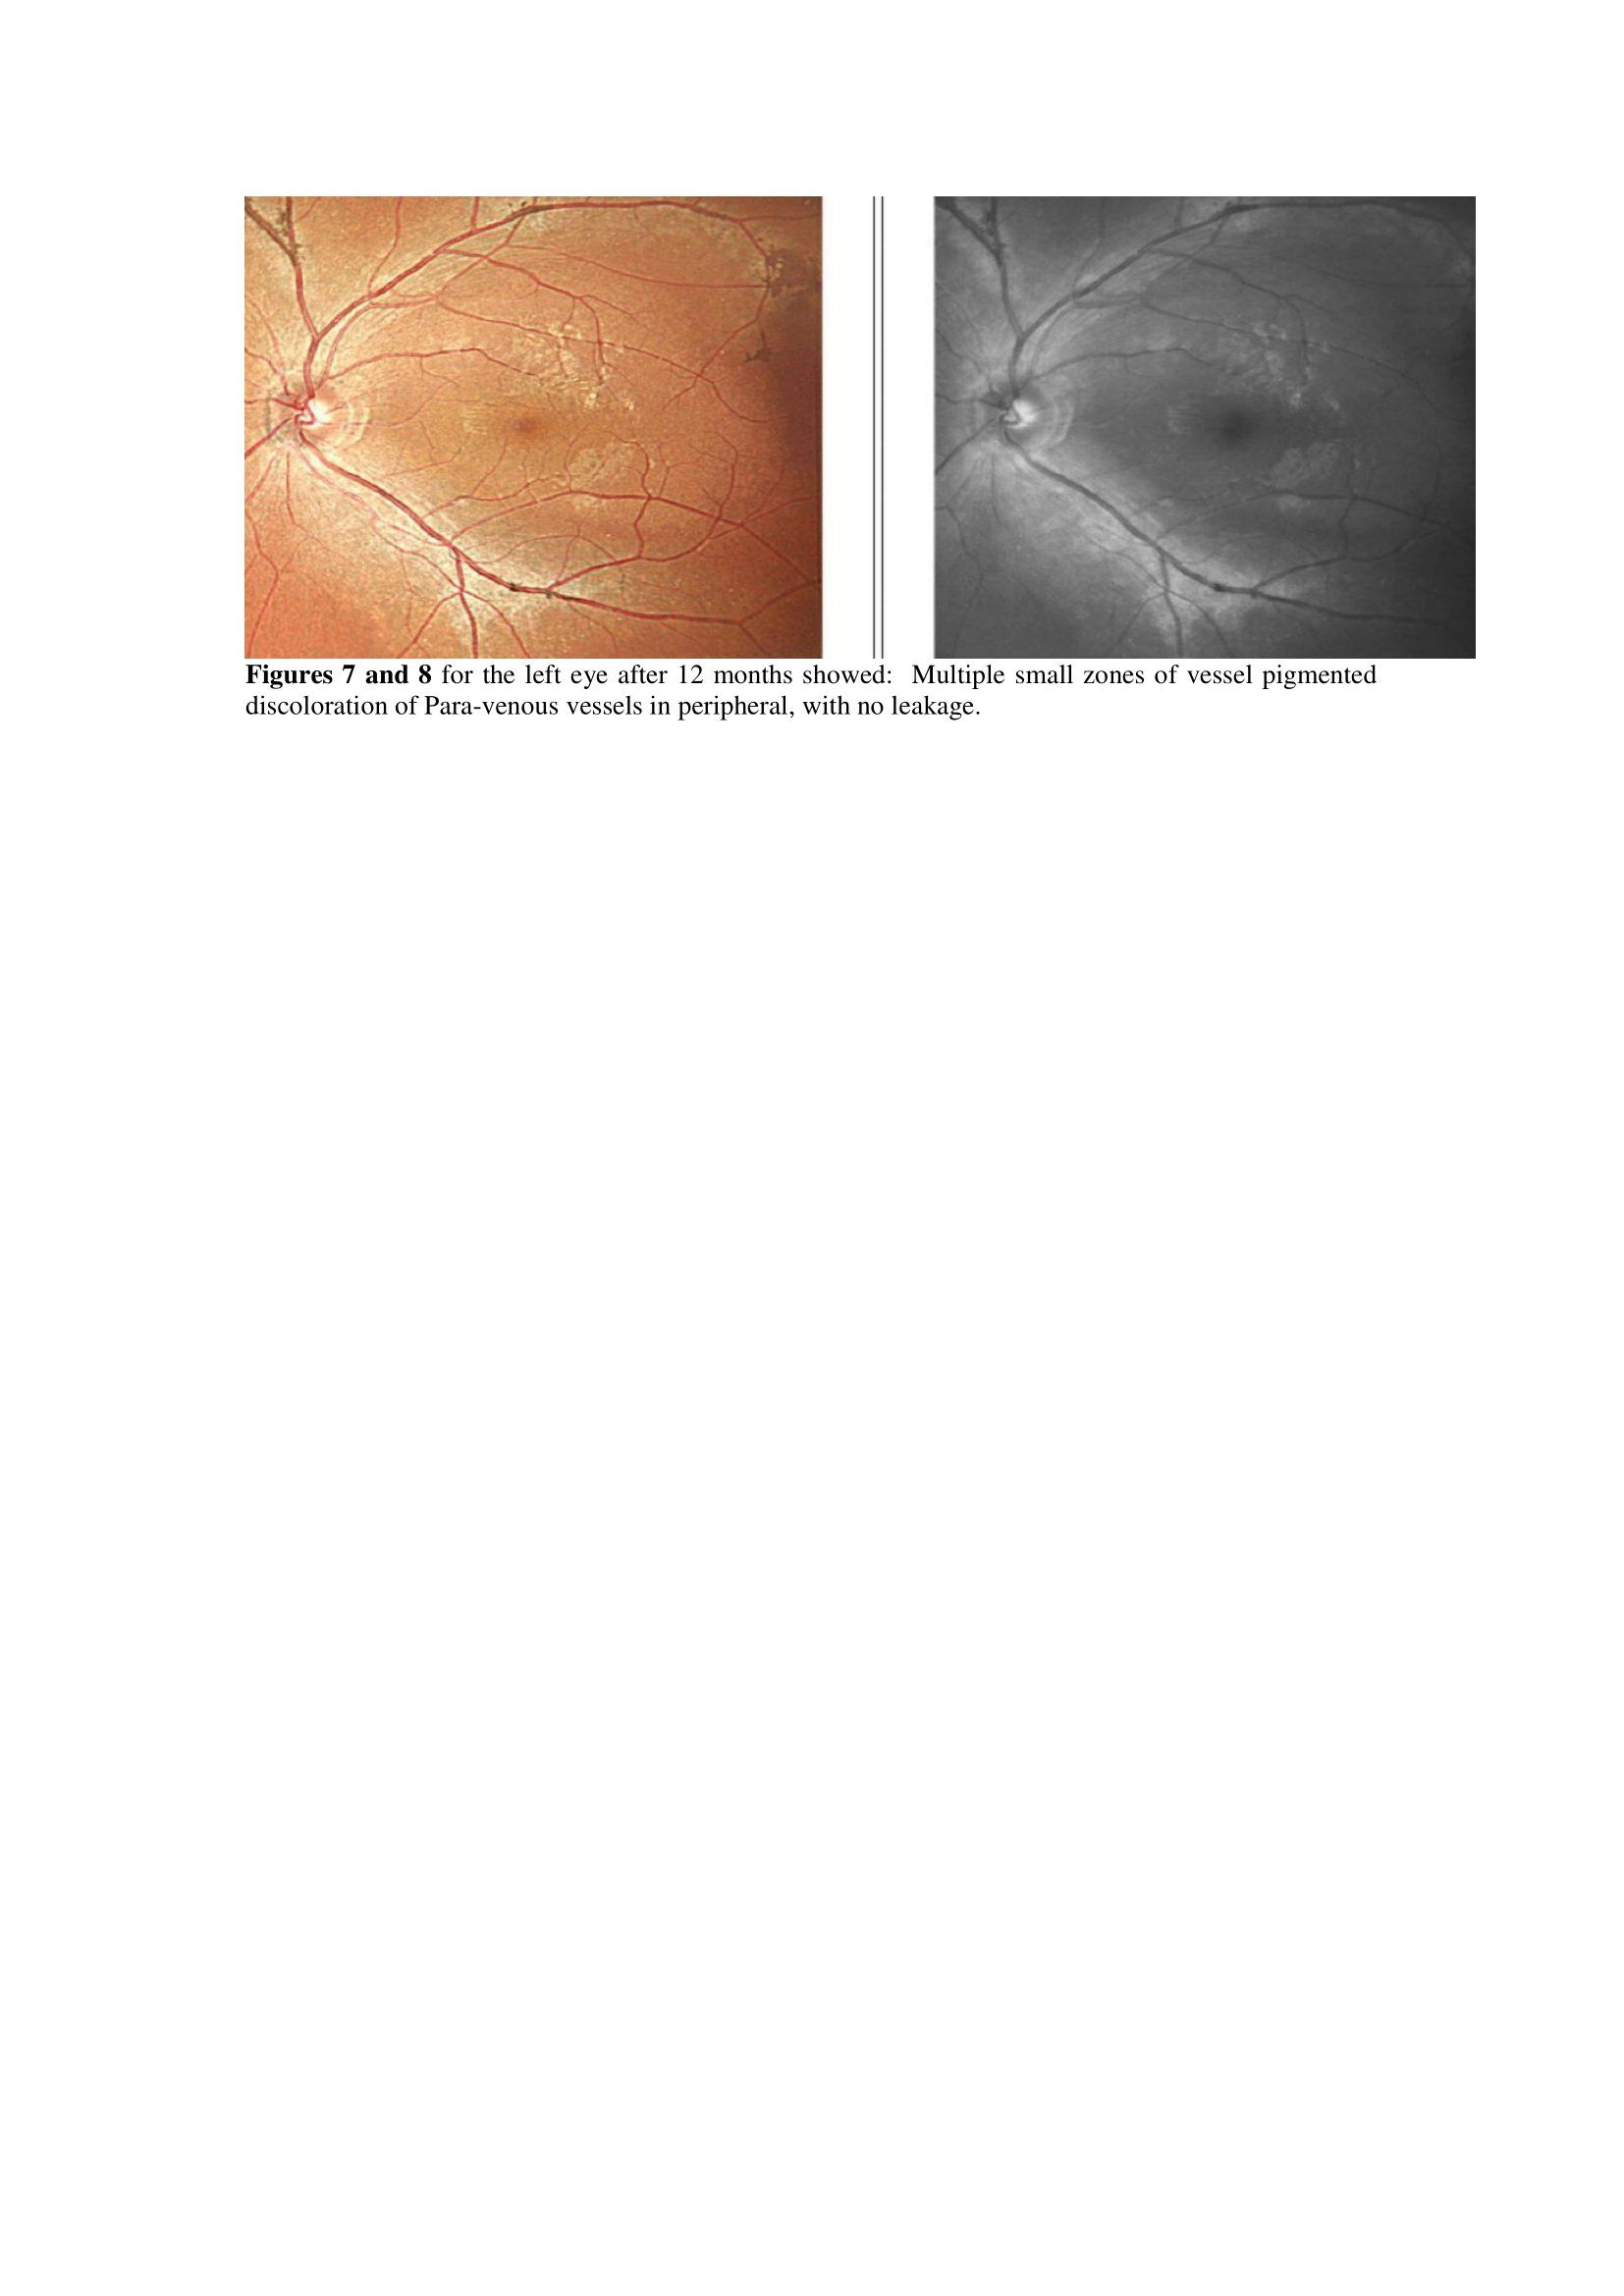

At 12 months, The patient full ophthalmology examination showed improvement of his vision of 6/6 in the right eye and 6/6 in the left eye, and his colour vision also showed marked improvement of red-green to 18/21 with Ishihara score for colour testing [7].

Fundus fluorescein angiography was done at 12 months, and showed the same malaria pigments along the blood vessels, but there was improvement of macular whitening with complete resolution. The patient retina photos at that visit at 12months are shown in figures 5, 6, 7 and 8) respectively.